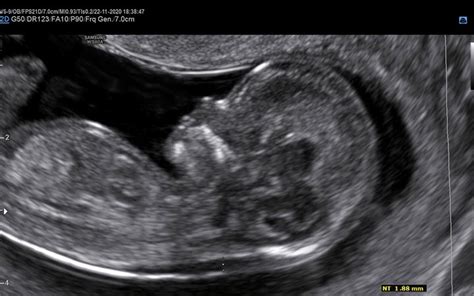

Nuhalna svetlina je sodobna, neinvazivna ultrazvočna preiskava, ki predstavlja temeljni presejalni test za zgodnje odkrivanje morebitnih kromosomskih in drugih nepravilnosti ploda. Izvaja se v obdobju med 11. in 14. tednom nosečnosti ter ponuja ključne informacije, ki bodočim staršem pomagajo pri razumevanju zgodnjega razvoja otroka in potencialnih tveganj. Preiskava, ki jo strokovno poimenujemo zgodnja morfologija ploda ali presejanje za kromosomopatije, poleg ocene tveganja za kromosomske napake, kot je Downov sindrom, temeljito preverja tudi pravilnost zgodnjega razvoja ključnih organov in struktur ploda.

Nuhalna svetlina (NS) je tekočina, ki se v prvem trimesečju nosečnosti nabere v podkožju na vratu ploda. Med ultrazvočnim pregledom zdravnik izmeri debelino te tekočinske plasti med kožo in mehkimi tkivi, ki prekrivajo hrbtenico ploda v zatilju. V tem obdobju razvoja je prisotnost določene količine tekočine normalna, vendar je pri plodovih s kromosomskimi napakami, kot so trisomija 21 (Downov sindrom), trisomija 18 (Edwardsov sindrom) in trisomija 13 (Patau sindrom), ter pri nekaterih srčnih napakah ali genetskih sindromih, ta plast običajno povečana.

Optimalni čas za izvedbo meritve nuhalne svetline je med 11. tednom nosečnosti (ko je plod dolg približno 45 mm) in 14. tednom nosečnosti (do 13 tednov in 6 dni, ko je dolg do 84 mm). Ta časovni okvir je ključen, saj v tem obdobju omogoča natančno merjenje in opazovanje ključnih parametrov. Pregled praviloma poteka z ultrazvokom preko trebušne stene (transabdominalno). V izjemnih primerih, na primer ob neugodnem položaju ploda ali večji telesni masi nosečnice, se lahko uporabi vaginalni ultrazvok.